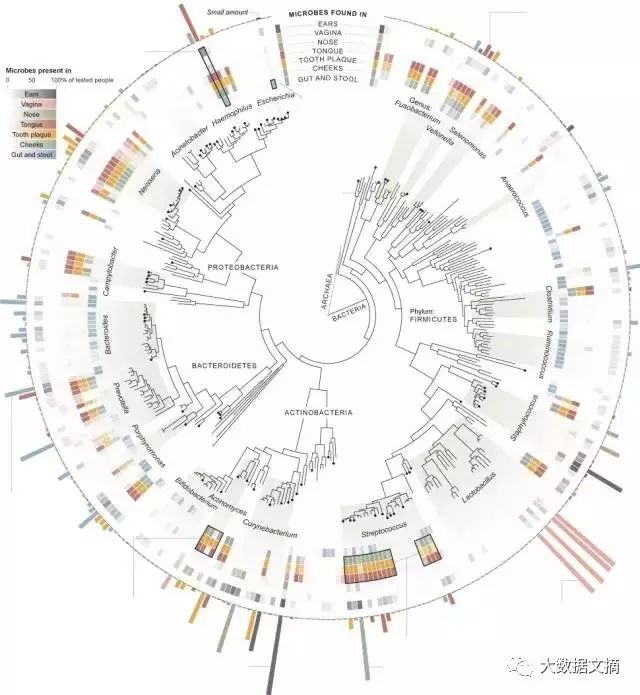

**87-**Tree of Life Leonard Eisenberg

生命之树